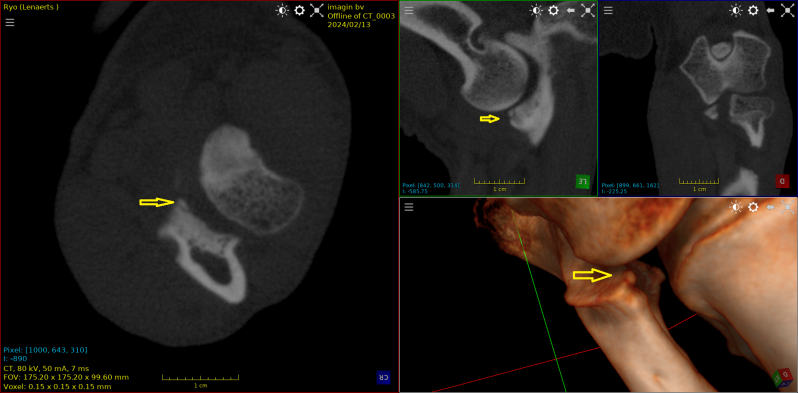

Deze Visla van 8 jaar werd aangeboden met een klacht van chronisch manken sinds 1 maand.

Op de scan is een  oud OCD - letsel zichtbaar met een gewrichtsmuis.

Het stukje werd operatief verwijderd.